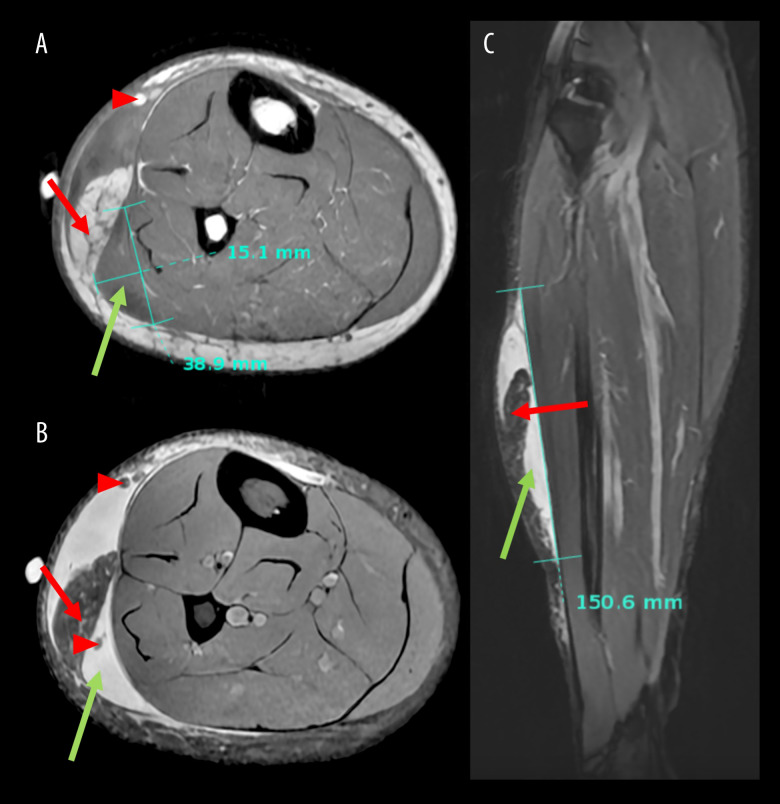

Morel-Lavallee病变(mls)是一种罕见的由高能外伤引起的闭合性软组织脱手套损伤,由于其罕见性和延迟表现而经常被遗漏,导致严重的并发症。在儿童和青少年患者中,mls尤其被遗漏和少报。我们描述了发生在小腿非典型病变部位的青少年MLL病例,以提高对该患者组的诊断和相关表现的认识,这可能不同于成人的表现,并导致诊断的不确定性,从而影响临床决策。病例报告一名18岁男性,在打篮球时滑到墙上,右外侧小腿出现疼痛和日益加重的肿胀。磁共振成像(MRI)显示液体收集最初怀疑是血肿。保守治疗失败后,多学科合作方法确认了MLL诊断,并通过超声引导下的抽吸引流病变。虽然患者已恢复所有正常的身体活动,但仍需对残余的肿胀和畸形进行监测。结论:我们的病例强调了诊断和治疗的挑战与非典型临床表现的MLL的青少年患者与运动损伤的小腿,突出的作用,影像学和多学科咨询在及时干预。与现有有限的mls文献一致,早期微创超声引导下的抽吸可能有利于指导后续治疗,但需要通过建立标准化的儿童和青少年管理指南来进一步研究和达成共识,以实现这一弱势患者群体的最佳临床结果。

BACKGROUND Morel-Lavallee lesions (MLLs) are uncommon, closed soft-tissue degloving injuries caused by high-energy trauma that are often missed due to their rarity and delayed presentation, resulting in serious complications. MLLs are particularly missed and underreported in pediatric and adolescent patients. We describe the case of an adolescent MLL occurring in an atypical lesion site at the calf to increase awareness of this diagnosis and associated presentation in this patient group, which can differ from adult presentation and contribute to diagnostic uncertainty that consequently impacts clinical decision-making. CASE REPORT An 18-year-old male presented with pain and worsening swelling in the right lateral calf after sliding into a wall while playing basketball. Magnetic resonance imaging (MRI) demonstrated a fluid collection initially suspected to be a hematoma. Following failed conservative management, a multidisciplinary collaborative approach confirmed a MLL diagnosis and drained the lesion via ultrasound-guided aspiration. While the patient has resumed all normal physical activities, residual swelling and deformity remain under surveillance. CONCLUSIONS Our case highlights the diagnostic and treatment challenges associated with an atypical clinical presentation of a MLL in an adolescent patient with a sports injury to the calf, highlighting the role of imaging and multidisciplinary consultation in timely intervention. Consistent with the limited existing literature on MLLs, early minimally invasive ultrasound-guided aspiration may be beneficial to guide subsequent treatment, but further study and consensus via establishment of standardized pediatric and adolescent management guidelines are necessary to achieve optimal clinical outcomes for this vulnerable patient population.